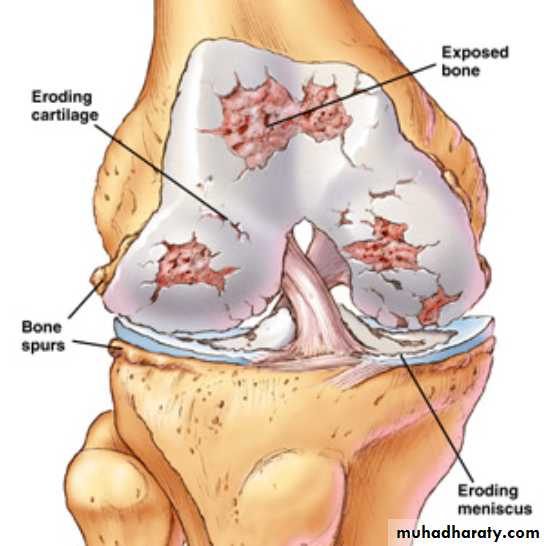

Characterised by:Focal loss of articular cartilage

Subchondral osteosclerosisOsteophyte formation at the joint margin

Remodelling of joint contour with enlargement of affected jointsInflammation is not a prominent feature

Genetic factors play a key role in the pathogenesis of OA, the heritability of OA ranges between about 43% at the knee to between 60% and 65% at the hip and hand, respectively.Major alterations in cartilage structure are characteristic of OA.

Chondrocytes divide to produce nests of metabolically active cells.Increased degradation of the major structural components of cartilage, including aggrecan and type II collagen

Fissuring of the cartilage surface (‘fibrillation’) development of deep vertical clefts, localised chondrocyte death and decreased cartilage thickness

The subchondral bone is abnormal, with osteosclerosis and subchondral cyst formation.

Fibrocartilage is produced at the joint margin, which undergoes ossification to form osteophytes.Bone remodelling and cartilage thinning slowly alter the shape of the OA joint, increasing its surface area.